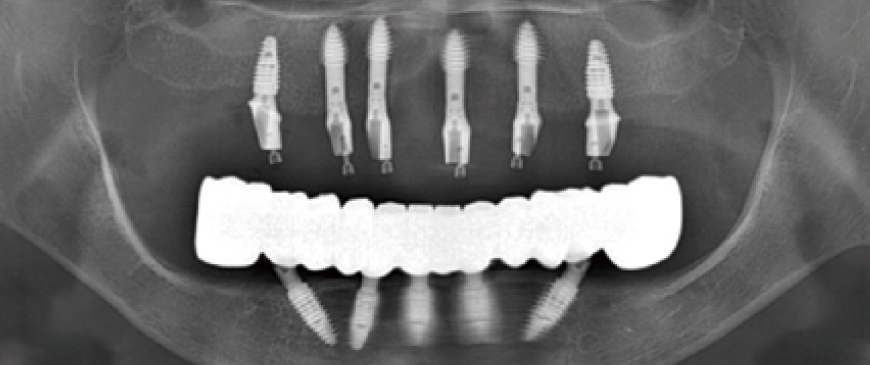

Four days after the surgery, custom abutments and a PMMA bridge were placed.

Fig 11

Panoramic image when custom abutments and PMMA bridge were placed.

Fig 12

The final prosthesis was placed approximately 3 months later, after the soft tissue stabilized.